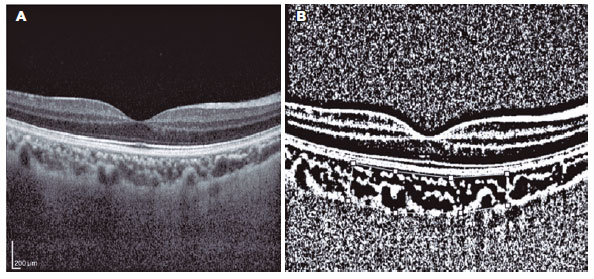

Binarization of the choroidal area was performed with the Image-J Version 1.50a software (National Institutes of Health, Bethesda, MD, USA; Figures 2 and 3). The EDI-OCT image was opened with Image-J, and 3000-µm wide areas with margins of 1500 µm temporal to the fovea was chosen. The choroidal area was defined as the region from the retinal pigment epithelium to the chorioscleral border, and the borders were set manually with the Image-J ROI Manager. Three choroidal vessels with lumens >100 µm were selected using the oval selection tool and the mean reflectivity of the luminal areas were determined. The Niblack method was used for the binarization of the choroidal image. Then, the image was converted to 8 bits and adjusted using the Niblack auto local threshold. The luminal area was determined with the threshold tool. After adding the distance between the pixels, the choroidal, luminal, and stromal areas were automatically calculated for the 2 groups. The light pixels were accepted as the stromal area; and the dark pixels, as the luminal area (12). The choroidal vascularity index (CVI) was calculated as the ratio between the luminal and total choroidal areas.

12-fig03tb.jpg)